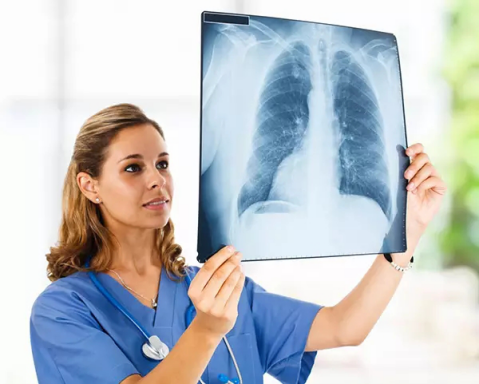

X光攝影(平片)

X光會(huì)穿透人體,由于人體各部位組織密度厚度不同,吸收的X光機(jī)的劑量不同,到達(dá)底片的X光的量不同,底片就會(huì)顯現(xiàn)出黑白不同的顏色。

優(yōu)點(diǎn):快捷、價(jià)廉、影像清晰度高

缺點(diǎn):平片檢查,無法進(jìn)行三維檢查

3、胸部——粗看X光平片,細(xì)看CT

X光胸片可粗略檢查肺、心影、主動(dòng)脈弓、肋骨等,可以檢查有無肺紋理增多、肺內(nèi)較大腫塊、主動(dòng)脈結(jié)鈣化等。胸部CT檢查顯示出的結(jié)構(gòu)更清晰,對胸部病變檢出敏感性和準(zhǔn)確性均優(yōu)于常規(guī)X光胸片,特別是對于篩查早期肺癌有重大意義。而磁共振成像對于肺內(nèi)疾病的診斷,應(yīng)用非常有限。